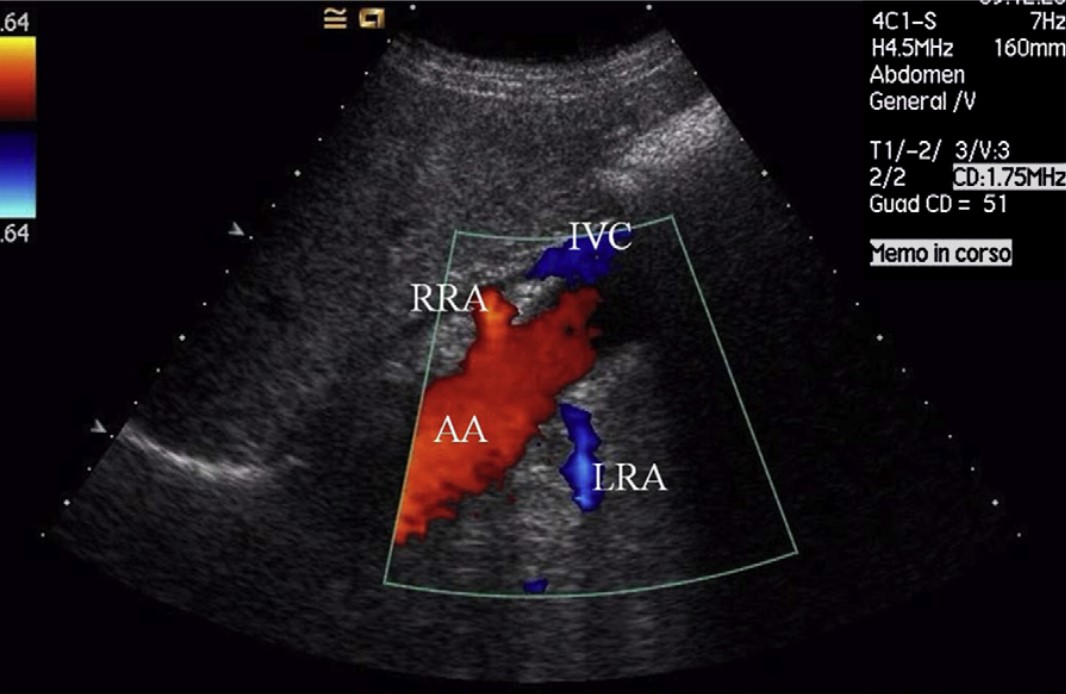

17 lis 2025 USG Doppler tętnic nerkowych – kiedy za wysokie ciśnienie „zaczyna się w nerkach”? Czytaj więcej